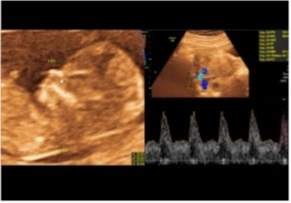

Ecografía Doppler 11-14 Semanas

Sirve para llevar un control específico de tu bebé, además de buscar en estas semanas marcadores de riesgos cromosómicos como síndrome de down, turner, etc. Pasadas las 14 semanas, ya no se puede contar con la fiabilidad esos marcadores.

Ecografía Obstétrica 3D/4D

Este estudio incluye la ecografía obstétrica, que revisa la anatomía del bebé y llevar un control de su peso. Se busca visualizar la carita del bebé. No requiere preparación previa.

Ecografía Obstétrica 5D

Este estudio incluye la ecografía obstétrica, que revisa la anatomía del bebé y llevar un control de su peso. Se busca visualizar la carita del bebé. No requiere preparación previa.